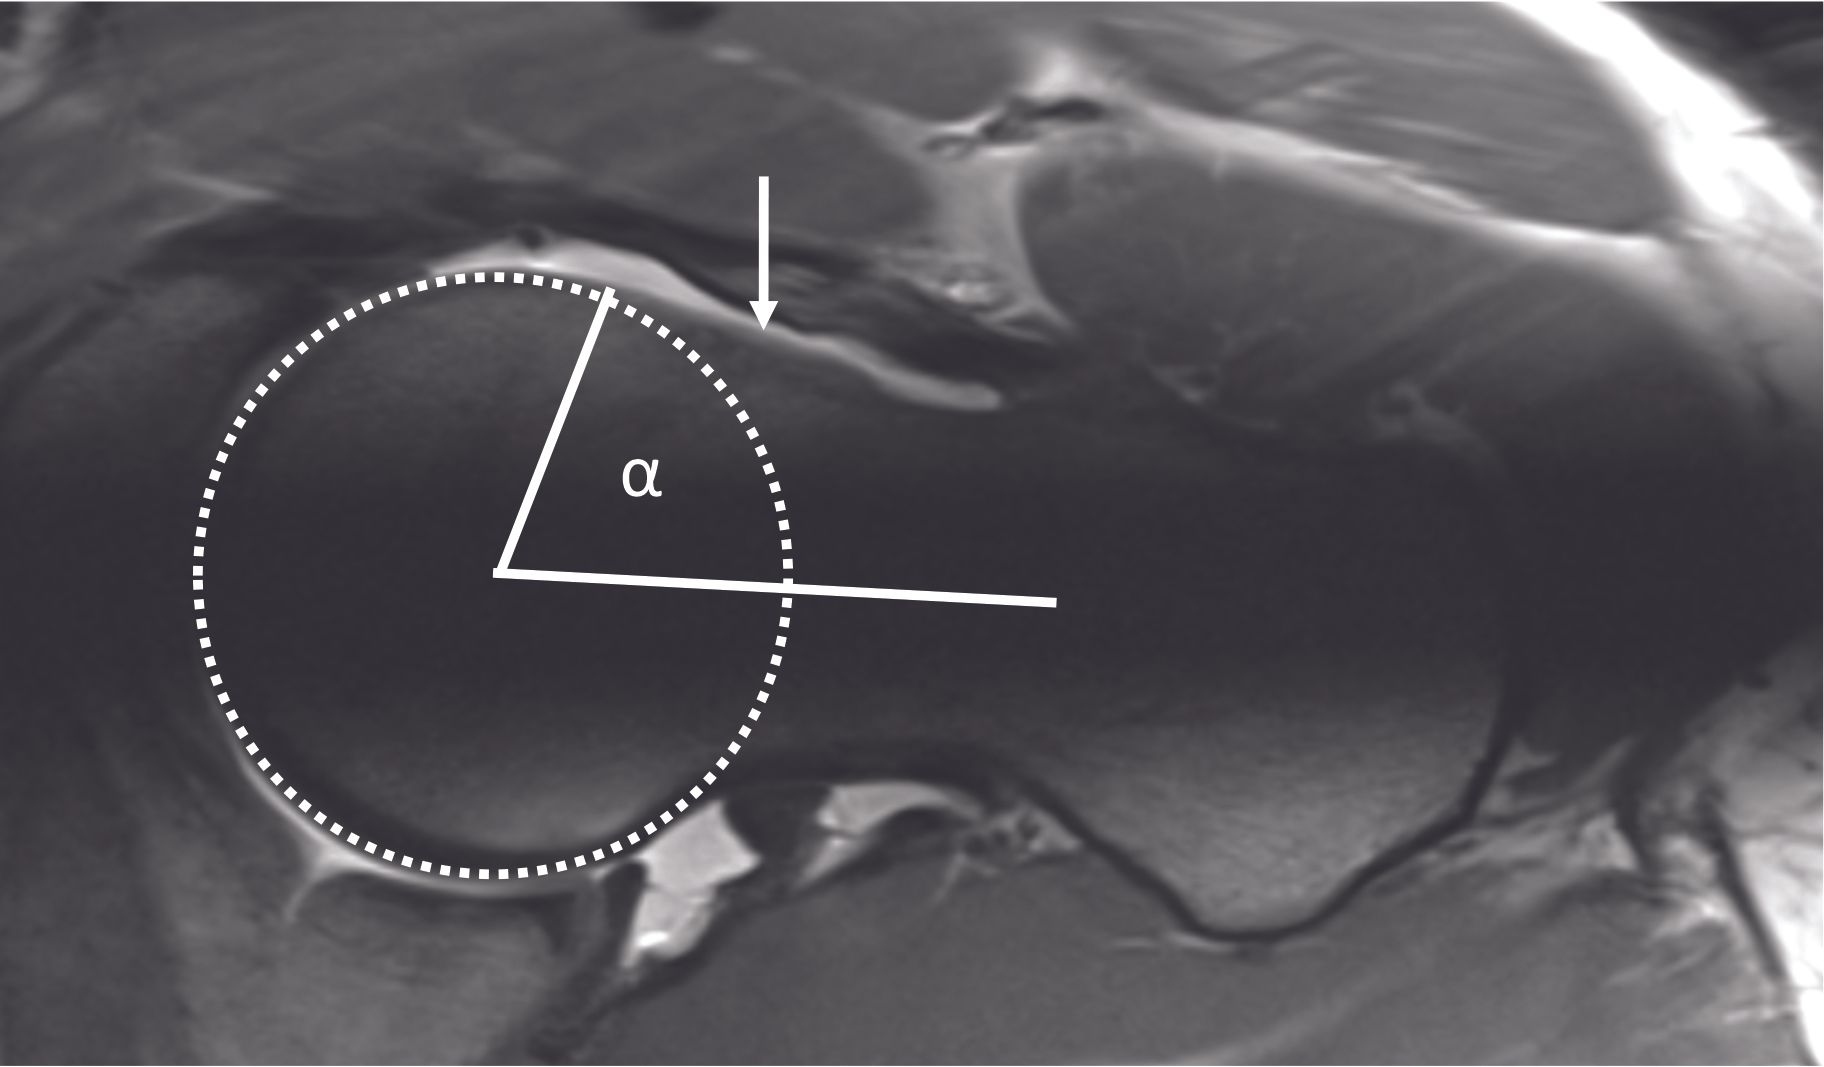

Finally, radiographs can exclude the presence of advanced arthritic changes, for which conservative hip surgery is no longer appropriate, and arthroplasty options should be considered. Arthro-MRI is the imaging procedure of choice for assessing the labrum and cartilage. Injection of contrast material into the hip joint allows better visualization of the labrum and cartilage. Lesions of the labrum (Figure 6) are most often found in the anterosuperior part of the joint. MRI with radial reconstructions allows better localization and quantification of the cam effect morphology (Figure 7). The alpha angle can also be measured on this imaging modality.